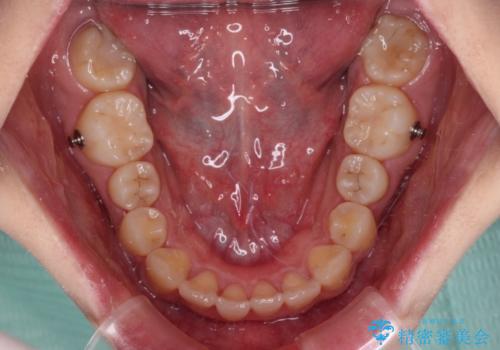

上顎前歯が捻れて前方に飛び出しており、下顎前歯もそれに沿うようにデコボコとなっていました。

IPR(歯と歯の間を削る処置)によりスペースを獲得して下顎前歯のデコボコを改善し、上顎前歯は下顎前歯と接する位置にまで引っ込めるように設定し、インビザラインにて矯正治療を行うこととしました。